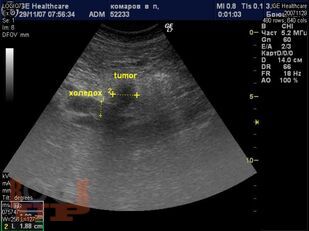

Учебно-методическое пособие посвящено актуальным проблемам этиологии, патогенеза, диагностики, современным методам консервативного и оперативного лечения механической желтухи. Представлены новые классификации, схемы консервативного лечения, современные виды оперативного лечения, учитывая утвержденные клинические рекомендации Российского общества хирургов (2018 г.). Издание иллюстрировано рисунками, таблицами, имеются тестовые задания и задачи. Пособие предназначено для слушателей дополнительного профессионального образования и ординаторов, обучающихся по специальности 31.08.67 Хирургия.